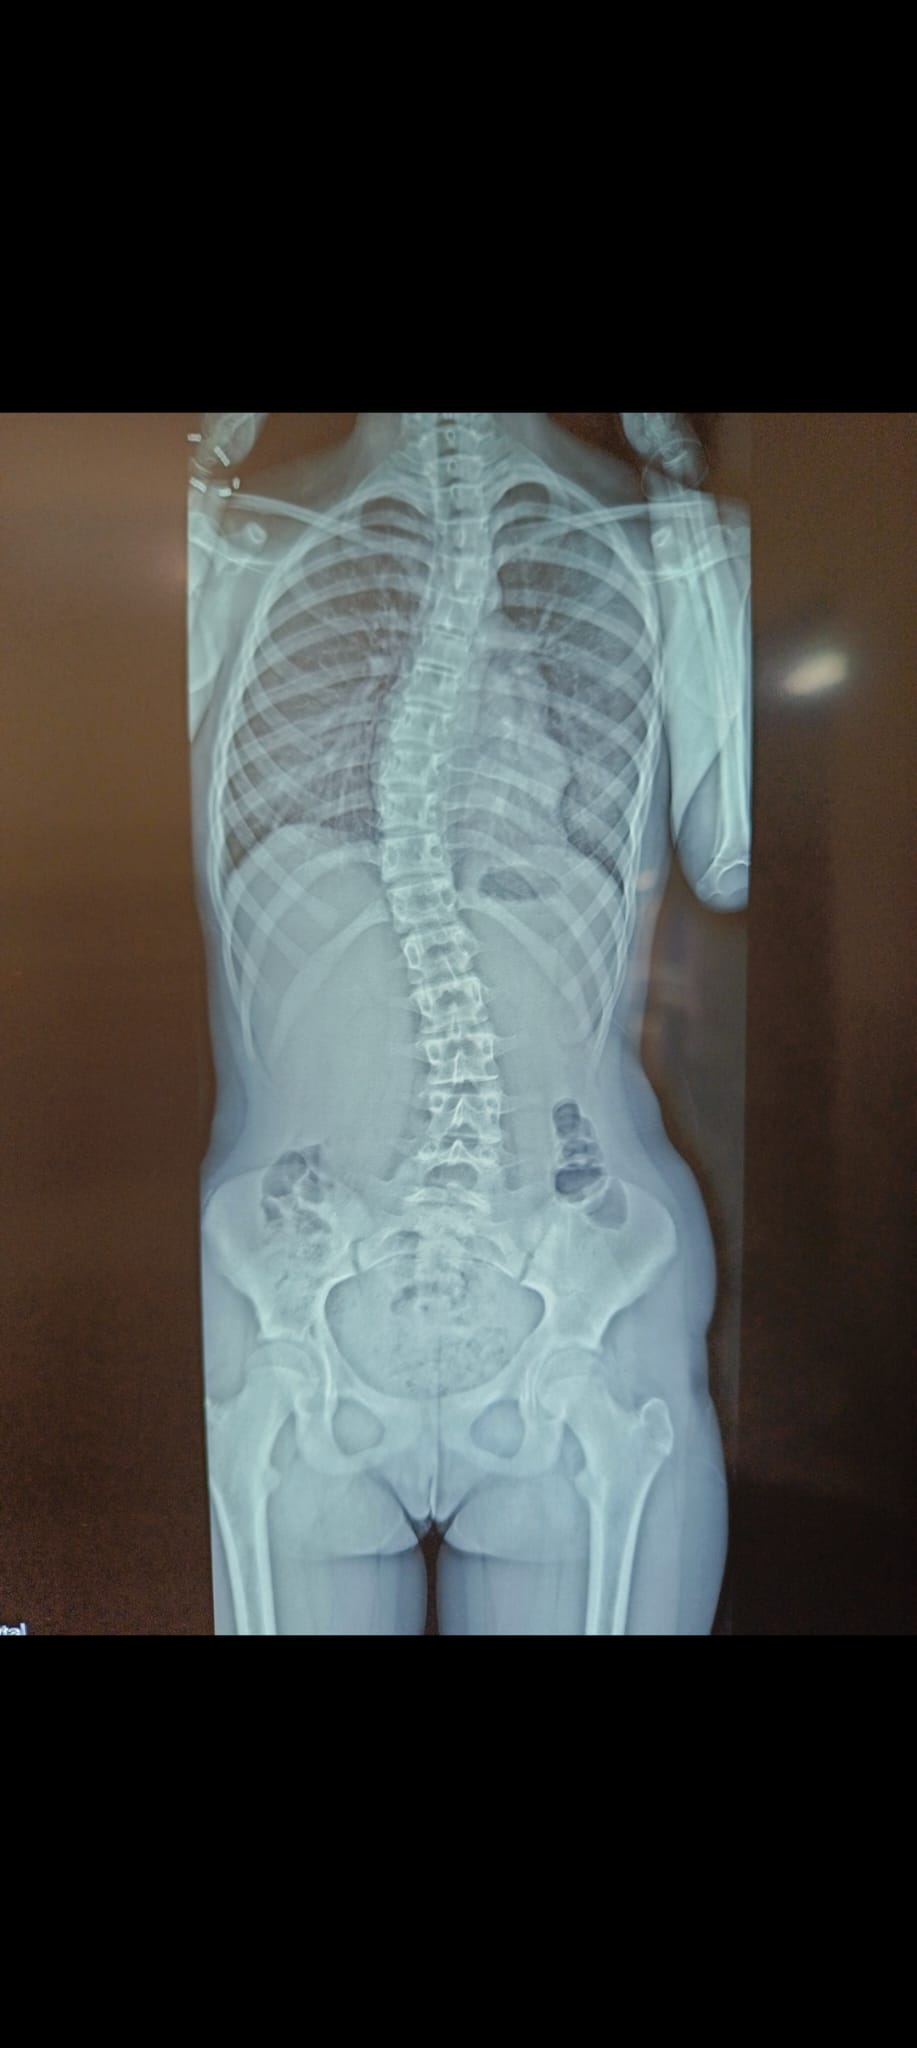

La scoliose est une déviation de la colonne vertébrale dans les 3 plans de l’espace. Celle-ci amène une silhouette asymétrique (visible au niveau des épaules et de la taille) et l’apparition de gibbosités (bosse), ainsi qu’un déséquilibre et une limitation de mouvement du tronc. Dans certains cas graves, la capacité respiratoire du patient peut se trouver limitée.

La scoliose est une pathologie qui se développe souvent pendant l’enfance et évolue progressivement au fil de la croissance. L’évolution est généralement lente dans période prépubère puis connait une accélération au moment de la puberté. Un examen médical est le seul moyen de détecter cette pathologie, les patients atteints ne souffrant en général pas de douleurs dorsales.

Le traitement se fait par appareillage au moyen d’un corset orthopédique sur mesure, moulé sur le corps et conçu de manière à permettre une croissance normale du rachis en corrigeant les déformations existantes.

Chaque corset est réalisé et adapté selon la morphologie du patient. Il tient compte de la déformation du rachis, du poids et de la taille de celui-ci, ainsi que de la prescription médicale. Selon la déformation du rachis et le modèle de corset prescrit, les temps de port de ce dernier peuvent être variables. De même des ajustements peuvent être réalisés selon l’évolution de la pathologie et de la morphologie du patient.